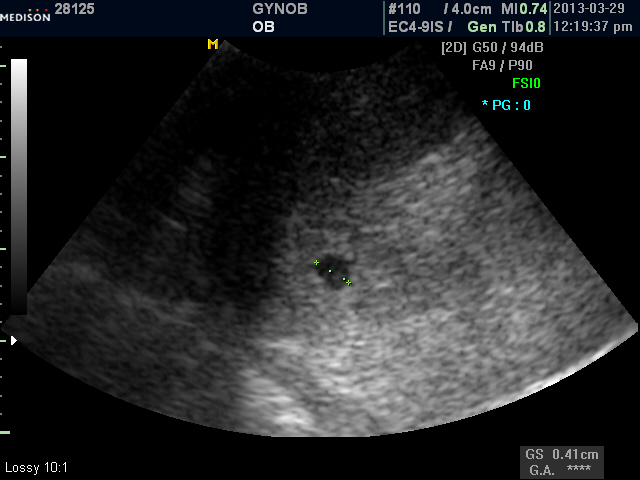

아기 집 보인다는 소식을 건너 듣고, 어찌나 기쁘던지!